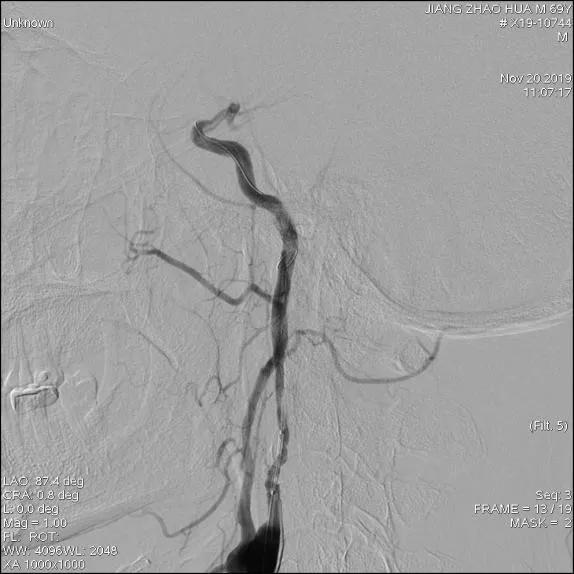

患者取仰卧位,常规消毒铺巾,Seldinger技术穿刺右股动脉,置入股鞘,引入8F导引导管至左侧颈总动脉分叉近端,造影提示:左侧颈内动脉近段肿瘤侵犯至狭窄,长约15mm,远端走形正常;后引入FilterWire EZ保护伞顺利通过狭窄段至C1远端,释放保护伞;引入4.5mm*16mm WILLIS®覆膜支架,精准定位后,缓慢球囊扩张释放支架。

WILLIS®支架到位

缓慢充盈球囊